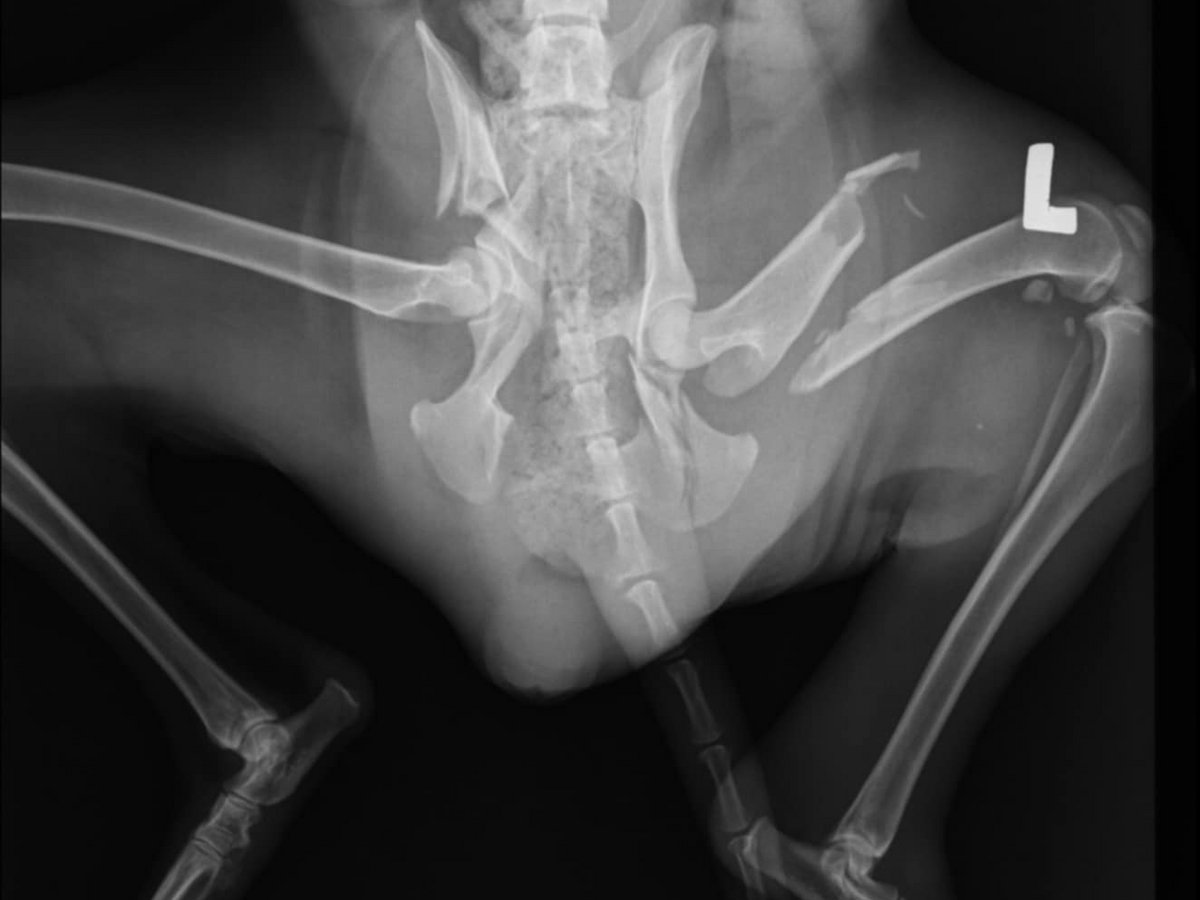

Jagdhündin "Hedda“:

Beckenbruch und Oberschenkelbruch. Sie wurde zur Operation nach Thessaloniki gebracht und hat den Eingriff gut überstanden. Sie muss in den nächsten Wochen noch gut gepäppelt werden, denn ihr Allgemeinzustand ist nicht der Beste.